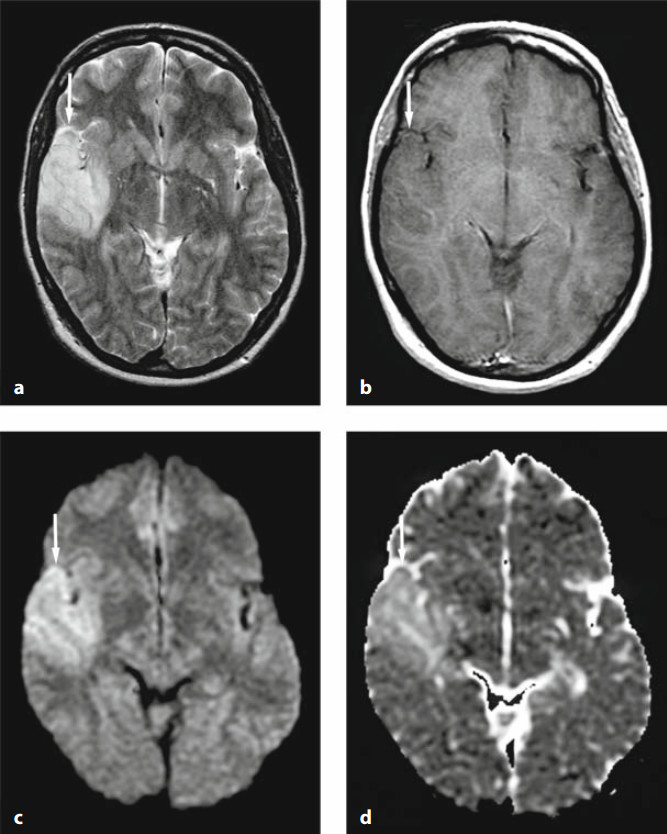

脑炎(包括病毒性脑炎、自身免疫性脑炎等)都有可能出现累及皮层 / 皮层下的 DWI 高信号。脑炎一般不难鉴别,急性起病,有发热、头痛等症状。累及皮层的脑炎会出现癫痫发作、精神症状等,行腰穿查脑脊液常规、生化、病毒抗体、自身免疫性脑炎抗体等可帮助诊断,图 1 为单疱脑炎患者发病 6 天时的磁共振检查结果。

图 1 单疱脑炎,起病 6 天,可见两侧颞叶病灶,右侧为甚,T2WI、FLAIR、DWI 均为高信号,ADC 图为低信号